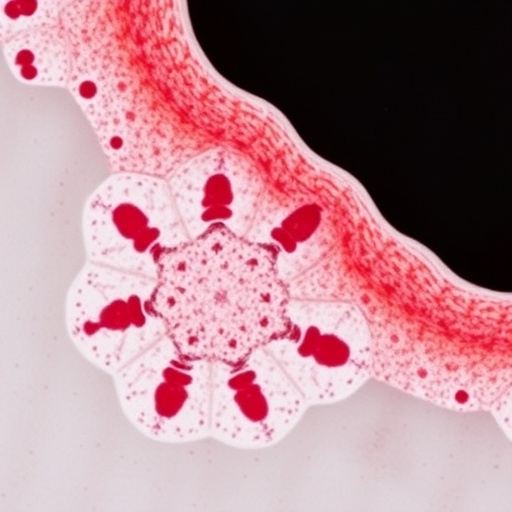

Omicron BA.2.86, JN.1 Broaden Intestinal Cell Tropism

In the ceaseless battle against SARS-CoV-2, the virus responsible for the COVID-19 pandemic, the scientific community continues to encounter new...